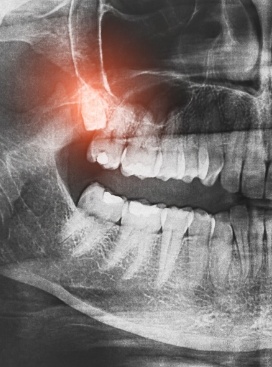

Wisdom Tooth Extractions

This is a surgical procedure that removes one or more wisdom teeth from your mouth. When wisdom teeth become impacted, they are stuck in your jawbone and gums and can cause pain and infection.